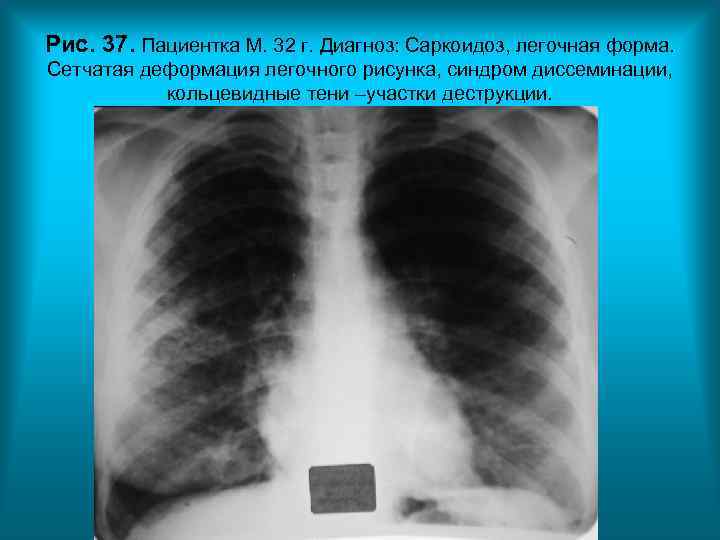

Рис. 37. Пациентка М. 32 г. Диагноз: Саркоидоз, легочная форма. Сетчатая деформация легочного рисунка, синдром диссеминации, кольцевидные тени –участки деструкции. Н. С. Воротынцева. С. С. Гольев Рентгенопульмонология